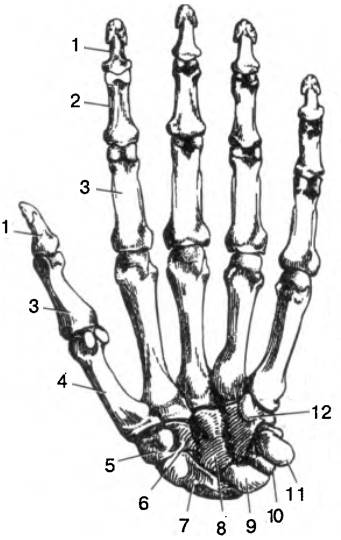

Анатомия кисти руки и строение костей